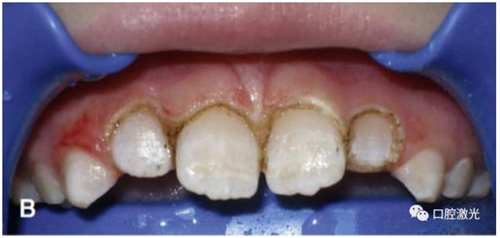

獲得理想的托槽粘接位置

正常情況下,理想的托槽粘接位置為牙冠的中心位置。如果要達到這一目的,正畸牙醫(yī)首先需要能夠從視覺上觀察清楚牙冠的整體形態(tài)。如果存在牙齦覆蓋、遮擋的情況,就很難達到這一目的。這時,簡單的激光牙齦切割就可以很好的增加牙冠的暴露程度,達到更加準確的粘接托槽的目的,從而也就加快了整個正畸療程的速度。通過下圖的病例可以看到,不僅患者節(jié)約了數(shù)月的等待時間,同時也創(chuàng)造了一個干凈的口腔環(huán)境,降低了在后續(xù)的正畸治療中可能導致牙齦增生的風險。

激光牙齦切割后暴露更多的上前牙便于粘接托槽